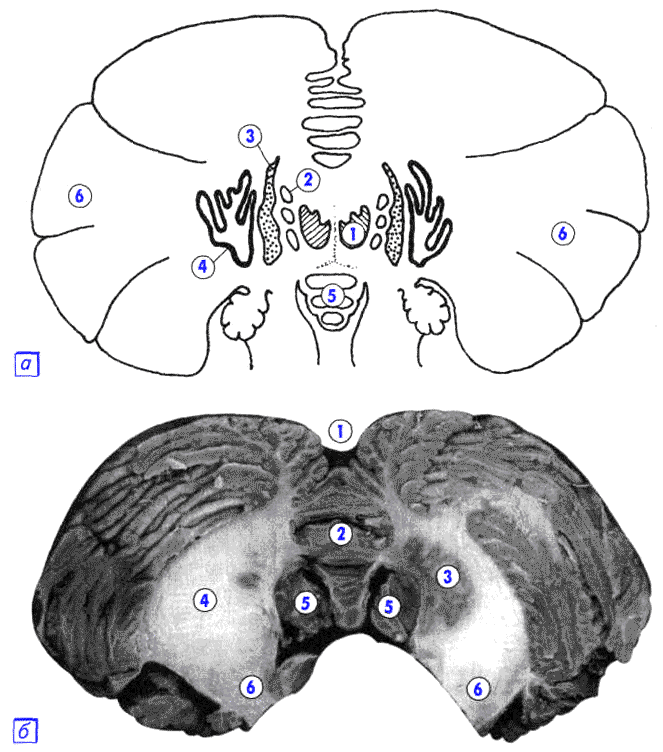

На рисунке: А. 1 – ядро шатра, 2 – шаровидное ядро, 3 – пробковидное ядро, 4 – зубчатое ядро, 5 – червь мозжечка, 6 – полушарие мозжечка. Б. 1 – задняя вырезка мозжечка, 2 – червь мозжечка, 3 – зубчатое ядро, 4 – мозговое ядро, 5 – миндалина, 6 – средняя ножка.